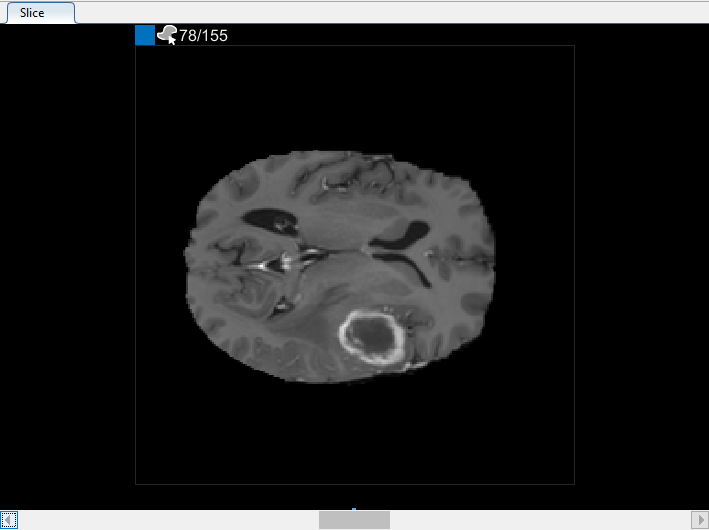

Можно также просмотреть каждый срез объема в панели Среза. Используйте ползунок в нижней части панели, чтобы переместиться от среза до среза. Вы видите опухоль на срезе 35 через срез 88. По умолчанию панель Среза отображает объем, ориентированный вдоль оси X-Y, но можно изменить это использование кнопки в разделе Orientation панели инструментов на вкладке Segmenter. Панель Среза также, где вы используете инструменты для рисования, чтобы задать маску.

С объектом, заданным на двух срезах, нажмите Auto Interpolate. Приложение автоматически задает ROI на всех прошедших слайдах. Приложение использует синие панели, чтобы указать на все срезы, которые имеют ROI, которые теперь появляются, когда тело запрещает срез 35, чтобы резать 88.